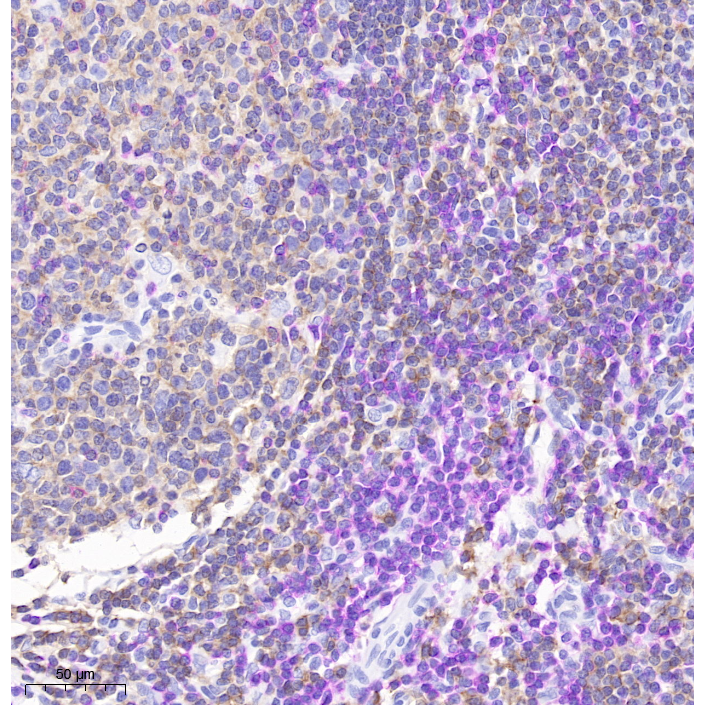

Human tonsil histochemical double staining: red chromogen-CD3 (pink), DAB-CD20 (brown)

Picture

Human tonsil histochemical double staining: red chromogen-CD3 (pink), DAB-CD20 (brown)